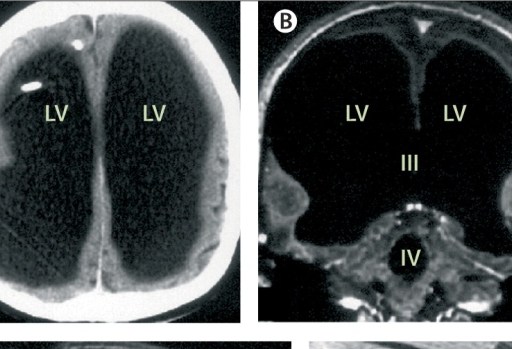

The man who lives a functional life with most of his brain filled with water challenges what we know about the brain.